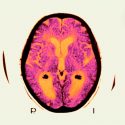

El solanezumab es un anticuerpo que barre las proteínas amiloides de la sangre y del líquido cefalorraquídeo. Las proteínas pueden pasar a formar placas en el cerebro. Eli Lilly, la compañía que desarrolló solanezumab, anunció el 23 de noviembre que abandonaría el fármaco como tratamiento para pacientes con demencia leve. El resultado se suma a una larga lista de fármacos de alzhéimer prometedores que han fracasado en la práctica clínica, muchos de los cuales, como el solanezumab, apuntan al amiloide.

El ensayo de Lilly, conocido como EXPEDITION3, involucró a más de 2 mil 100 personas diagnosticadas con demencia leve debido a la enfermedad de Alzheimer. La mitad recibió inyecciones mensuales de solanezumab y la otra mitad placebo. Fueron seguidos durante 18 meses y probados en una serie de tareas cognitivas. El análisis de personas con síntomas comparables en estudios anteriores de solanezumab parecía alentador, pero este último ensayo indicó solo un pequeño beneficio, insuficiente para justificar la comercialización de la droga.

El resultado de Lilly podría decir más sobre las características del solanezumab que la exactitud de la hipótesis subyacente del amiloide, dice Christian Haass, jefe de la rama de Múnich del Centro Alemán de Enfermedades Neurodegenerativas. El anticuerpo se dirige a las formas solubles de amiloide, señala, por lo que «podría ser atrapado en la sangre sin llegar a alcanzar el objetivo real en el cerebro en cantidades suficientes».